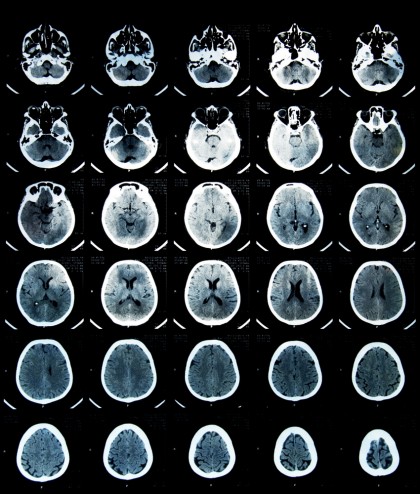

Stimularea electrică a creierului - benefică sau dăunătoare?

Ca mod de funcționare, dispozitivele utilizează electrozi care permit transmiterea ușoară a impulsurilor electrice spre creier, provocând activitatea specifică zonelor cerebrale stimulate. Așadar, teoretic, un astfel de aparat ar trebui să garanteze oricărui utilizator îmbunătățirea abilităților cognitive. Cu toate actestea, practica arată contrariul.